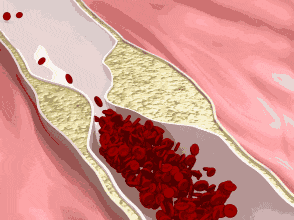

Il suffit de comprendre que la carotide, ou grande artère du cou, qui est le principal vaisseau sanguin de l'organisme alimentant le cerveau, s'est rétrécie. Le terme professionnel est l'athérosclérose, le terme populaire est l'accumulation de déchets vasculaires. En cas de plaque carotidienne grave, une fois que la rupture se produit, il y a thrombose, puis le thrombus bloque les vaisseaux sanguins cérébraux, ce qui provoque un infarctus cérébral.

1, La formation de la plaque carotidienne estMaladies dans lesquelles de multiples facteurs s'accumulent au fil du tempsSes principalesChangements dans la composition du sangquiAnomalies du métabolisme des lipidesPour le principal, l'accumulation continue de LDL dans la paroi du vaisseau conduit à une augmentation du taux de cholestérol.Épaississement de la paroi du vaisseau au niveau centripèteDes plaques d'athérosclérose se forment dans les artères du cerveau et des reins. Les plaques peuvent apparaître à différents endroits : dans le cou (plaques carotidiennes), dans l'artère cérébrale moyenne (plaques de l'artère cérébrale moyenne), dans l'artère rénale (plaques de l'artère rénale), et ainsi de suite, la gravité et le type de maladie variant selon les parties du corps.

2, la plaque d'athérome n'est pas en soi toxique et nocive, la raison du traitement de la plaque est que la formation de la plaque conduit au rétrécissement de la lumière du vaisseau sanguin, rendant difficile le passage du flux sanguin, et les tissus distaux du vaisseau sanguin rétréci sont ischémiques et hypoxiques, ce qui conduit à l'émergence d'un certain nombre de symptômes cliniques. L'accumulation et l'épaississement continus de la plaque peuvent entraîner une grave détérioration de l'état de santé, qui aboutira finalement à une nécrose ischémique, telle que l'infarctus cérébral, l'infarctus cardiaque, la gangrène des mains et des pieds, etc.

3. La plaque carotidienne doit faire l'objet d'une attention particulière, la cause de l'accident vasculaire cérébral étant en partie due à la formation de la plaque carotidienne.Elle entraîne une nécrose ischémique et hypoxique des tissus cérébraux, ou une instabilité et un délogement de la plaque conduisant à un blocage vasculaire et à un infarctus cérébral, souvent appelé embolie cérébrale. En conséquence, des symptômes cliniques tels qu'une altération des mouvements des membres, des troubles de la conscience, des troubles cognitifs et des troubles de l'élocution apparaissent. Si les symptômes susmentionnés apparaissent, il est très difficile pour le patient de se rétablir avec un traitement de sauvetage. Le traitement de la plaque carotidienne est un traitement préventif visant à réduire la formation de la plaque et à élargir la lumière du vaisseau sanguin afin d'augmenter le flux sanguin, ce qui peut réduire considérablement le risque d'infarctus cérébral.